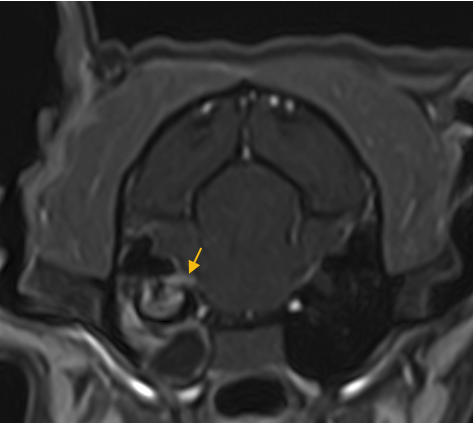

미세 뇌손상 정밀 확인(DWI)

아주 작은 손상·미세출혈 변화까지 확인에 도움됩니다.

(참고사진 : 2mm 이내의 미세 뇌출혈 환자)